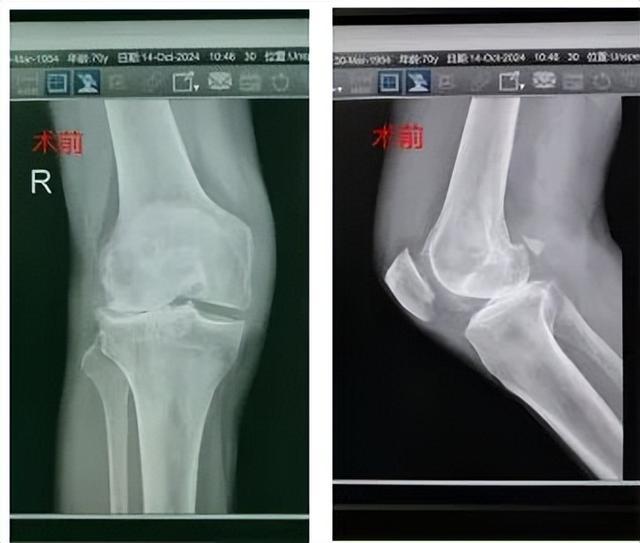

70岁李爹右膝关节疼痛长达10年,最近因摔伤症状进一步加重。为寻求中西医结合治疗,他慕名前往湖南省中西医结合医院(湖南省中医药研究院附属医院)关节外科就诊。

经过仔细评估,罗海恩主任团队决定为他实施一种相对微创的治疗方案——单髁置换术,手术仅60分钟便圆满完成。术后配合中西医结合快速康复,李爹当天就能下地活动,恢复情况令患者及家人惊喜。